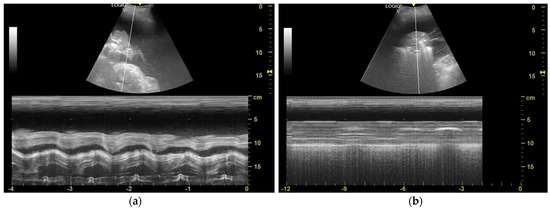

| Lichtenstein et al. [13] | 2008 | Evaluate TUS in acute respiratory failure (BLUE protocol) | Prospective observational study | Critically ill patients with respiratory distress | M-mode, B-mode | Identified sinusoid sign as indicative of lung expansion | Standardized lung ultrasound use in emergency settings | Limited generalizability beyond emergency care |

| Salamonsen et al. [15] | 2014 | Assess M-mode US for predicting NEL | Prospective observational study | 81 patients with MPE | M-mode, speckle tracking imaging (STI) | M-mode displacement <0.8 mm predictive of NEL | Allowed pre-drainage identification of entrapped lung | Some misclassification due to incomplete drainage |

| Flora et al. [16] | 2017 | Correlate sinusoid sign with pleural manometry | Prospective observational study | 10 patients undergoing thoracentesis | M-mode | Presence of sinusoid sign correlated with lung re-expansion | Suggested US as non-invasive alternative to pleural manometry | Small sample size |

| Leemans et al. [17] | 2018 | Investigate predictors of successful talc pleurodesis in malignant pleurisy | Retrospective study | 155 patients undergoing talc pleurodesis | M-mode | M-mode displacement <2 mm correlated with pleurodesis success (91% sensitivity, 88% specificity) | Highlighted role of M-mode in predicting pleurodesis success | Retrospective design, limited validation cohort |

| Wong et al. [18] | 2019 | Case report on absent sinusoid sign and trapped lung | Case report | 1 patient with metastatic breast cancer | M-mode, B-mode | Absent sinusoid sign correlated with high pleural elastance | Suggested pre-thoracentesis US assessment | Single case, needs validation |

| Hassan et al. [21] | 2021 | Validate TUS predictors of NEL | Prospective cohort | 29 patients with pleural effusion | M-mode, lung/liver echogenicity (LLE) ratio | M-mode alone was a poor predictor (AUC = 0.48), LLE ratio was better (AUC = 0.77) | LLE may serve as a better predictor for NEL than M-mode alone | Small sample size, single-center study |

| Khatim et al. [22] | 2022 | Diagnosis of NEL using TUS | Case report | 1 patient with small cell lung cancer and recurrent MPE | M-mode | Blunted cardiophasic variability indicated NEL, confirmed by post-drainage imaging | Highlighted importance of pre-procedural TUS assessment for NEL | Single case, limited generalizability |

| Petersen et al. [23] | 2024 | Compare M-mode, B-mode, and SWE for NEL prediction | Prospective observational | 49 patients with suspected MPE | M-mode, B-mode, 2D shear wave elastography (SWE) | M-mode had highest AUC (0.81) for NEL prediction | Reinforced M-mode as core tool for pleural disease assessment | Small sample, single-center variability |